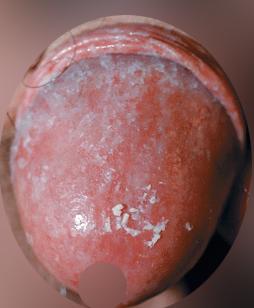

• 1번 째 사진

• 우선 귀두 전반에 균일한 발적이 있고, 표면에 하얀 찌꺼기처럼 보이는 부착물이 관찰됩니다. 작은 구진이 산재해 있으나, 수포나 궤양 형태는 보이지 않습니다. 위 사진이 전형적인 칸디다 포피염 입니다.

헤르페스의 전형적인 임상 양상은 초기에는 작고 군집된 물집이 나타나며, 이 수포가 터지면서 얕은 궤양으로 진행하고, 이 과정에서 통증이 비교적 뚜렷하게 동반되며 경우에 따라 배뇨 시 통증도 함께 나타나는 특징을 보입니다. 게다가 본인은 성관계를 맺지않았는데, 헤르페스 수포가 어떻게 걸리겠습니까.